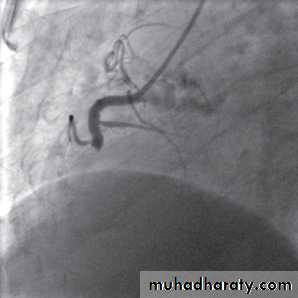

Reperfusion therapy: primary PCI

Associated with better results than thrombolytic therapy

Requires specialized experience and expensive equipment

Should be performed as soon as possible (minutes mean muscles)

Indicated in cases of failure of thrombolytic therapy or when such therapy is contraindicated.